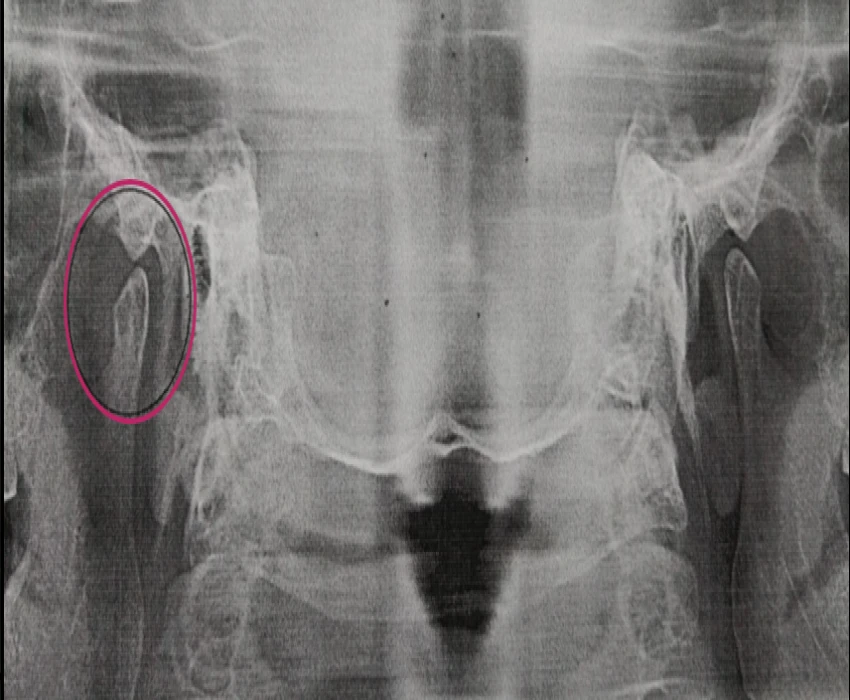

Reverse panoramic Radiography is a useful and promising technique for the initial preliminary imaging of the various anatomic structures like temporomandibular joint and its associated structures, mastoid air cell, lambdoid suture and occipital region and can be further explored in the near future.